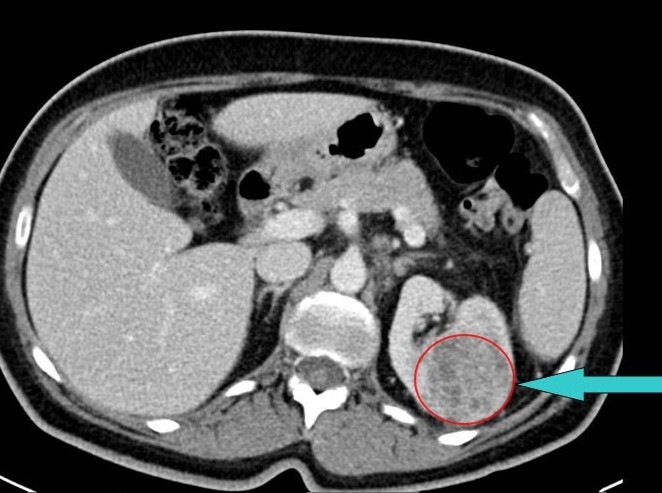

Muž 45 let – potíže s mikcí

Jste lékař urolog a přichází k vám pacient odeslán od praktického lékaře (PL). PL k Vám odesílá muže ve věku 45 let, pro nespecifické mikční potíže, které se objevily po prochlazení. Krev v moči pacient nepozoroval, lékařem to však nebylo došetřeno. Pacient nebyl doposud urologicky sledován, neléčil se.